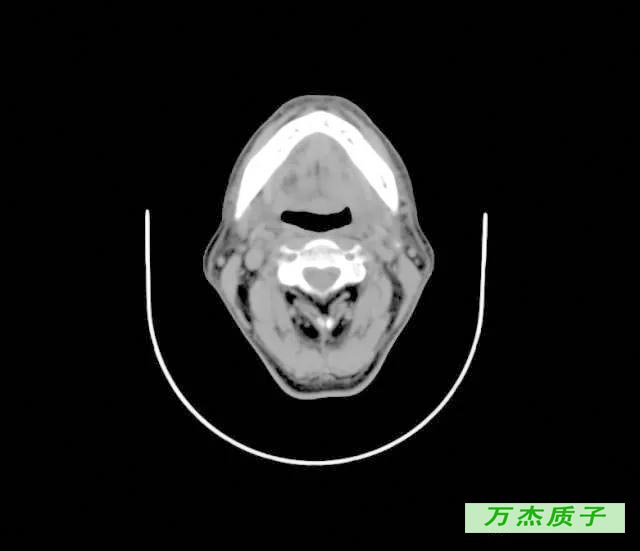

舌癌治愈率是多少 发布时间: 61次浏览 舌癌大家不会陌生,它是口腔颌面部常见的恶性肿瘤,发病率越来越高,严重的危害了我们的健康,有些舌癌患者会担心一个问题,舌癌的治愈率是多少,这关系到患者的人身安全。 舌癌的颈淋巴结转移率为29%~38%,与病程早晚期相关。治疗舌癌,先采用放射治疗而不应急于手术。直径在2厘米以下的治愈率,可高达%。 舌癌治疗 ( 一 ) 舌癌的一般疗法 (1) 舌癌患者因舌痛、舌肿大、溃烂、出血等影响进食 , 进食可以流质和半流质为主。

舌癌临床表现 编辑 播报 1肿瘤多发生于舌缘,其次为舌尖、舌背及舌腹等处,可有局部白斑病史或慢性刺激因素。 2常为溃疡型或浸润型,生长快,疼痛明显,浸润性强。 3可有舌运动受限、进食及 吞咽困难 。 4早期常发生颈淋巴结转移。舌癌诊疗知识 就诊科室: 肿瘤科 口腔科 治疗费用: 不同医院收费标准不一致,市三甲医院约( —— 元) 治愈率: 治疗周期: 治疗方法: 药物、手术治疗舌癌的治愈率有多大? 如果不能彻底治好,大约能活多久? _百度知道 舌癌的治愈率有多大? 如果不能彻底治好,大约能活多久? 首页 在问 全部问题 娱乐休闲